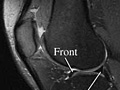

Magnetic Resonance Imaging (MRI) of the Knee

Magnetic resonance imaging (MRI) is a test done with a large machine that uses a magnetic field and pulses of radio wave energy to make pictures of the knee. Muscles, ligaments, cartilage, and other joint structures are often best seen with an MRI. In many cases an MRI gives information about structures in the body that cannot be seen as well with an X-ray, ultrasound, or CT scan.

For an MRI test, you are placed inside the magnet so that your knee is inside the strong magnetic field. An MRI can find changes in the structure of organs or other tissues. It also can find tissue damage or disease, such as infection or a tumor. Pictures from an MRI scan are digital images that can be saved and stored on a computer for further study. The images also can be reviewed remotely, such as in a clinic or an operating room. Photographs or films of selected pictures can also be made.